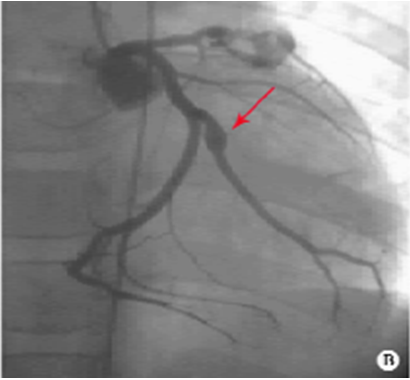

CoronaryAngiography (冠状动脉造影)

左、右冠状动脉巨大冠脉瘤伴血栓形成

左前降支巨大冠脉瘤内有血栓,远端狭窄

回旋支冠脉瘤

右冠脉巨大冠脉瘤伴狭窄